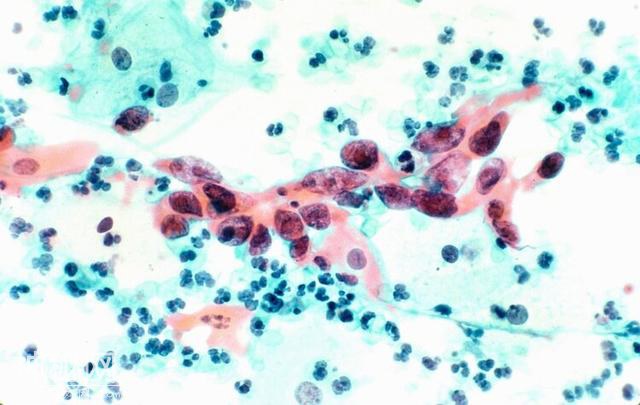

放射性碘125粒子体型微小,一般直径不足1mm,长不足5mm,但具有非常大的能量,当多颗粒子精准分布植入到肿瘤中时,它们聚集后能有力抗击多种肿瘤。

东南大学附属中大医院介入科专家表示,目前碘粒子疗法已让5000余名癌症患者总体缓解率超九成。

对于癌症患者,在植入碘粒子之前,医生团队一般会通过CT或B超设备,对肿瘤部位进行准确定位。随后在影像引导下经过穿刺,悄悄将直径碘粒子植入肿瘤组织内。

碘粒子植入可以在长期里由内向外地摧毁肿瘤细胞,且它对多种肿瘤都有一定治疗作用。